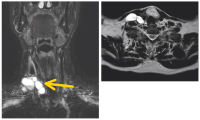

MR-Angiographie

Abbildung 2: T2-gewichtete Aufnahmen der MR-Angiographie zeigen die extratrunkalen und trunkalen (Aneurysma der Vena poplitea, Pfeil) der venösen Malformation.

Keywords: GefäßmedizinMR-AngiographieVena popliteavenöse Malformation